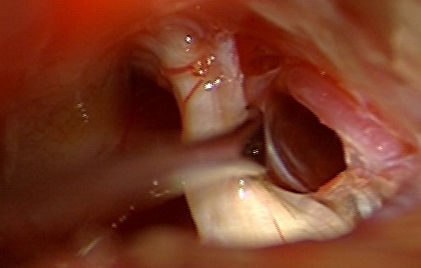

Sinoviāla cista

Redzama L4-5 līmeņa sinoviāla cista

Pēc operācijas sinoviālā cista vairs nav redzama